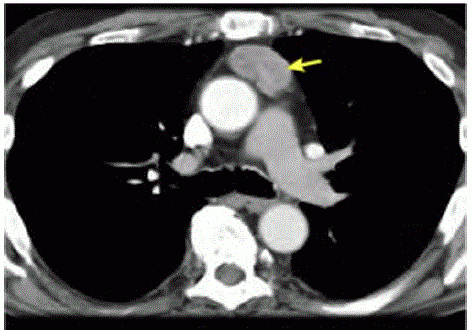

Ulna paciente de 47 anos de idade, com sint01nas gripais agudos, realizou exames de imagem de tórax por suspeita de Covid-19. A hipótese não se confirmou, porém a tomografia computadorizada de tórax, representada pela imagem a seguir, evidenciou uma massa heterogênea de contornos bem definidos em topografia de mediastino anterior, em localização de timo, de aproximadamente 4,5 cm x 2,9 cm. Não apresentava linfonodos aumentados no exame de imagem. Realizaram-se , ainda, tomografias computadorizadas de encéfalo e de abdome, que não mostraram alterações.

Acervo Pessoal

A lesão em apresentada na imagem pode estar associada a doenças autoimunes, como lúpus eritematoso sistémico, artrite reumatoide , anemia perniciosa e tireoidite.

A paciente descrita pode ser portadora de miastenia gravis.